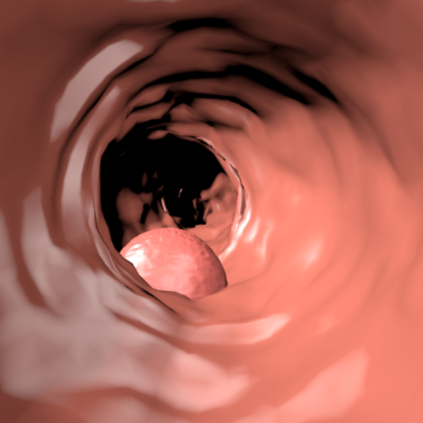

Deep learning has shown excellent performance in analysing medical images. However, datasets are difficult to obtain due privacy issues, standardization problems, and lack of annotations. We address these problems by producing realistic synthetic images using a combination of 3D technologies and generative adversarial networks. We use zero annotations from medical professionals in our pipeline. Our fully unsupervised method achieves promising results on five real polyp segmentation datasets. As a part of this study we release Synth-Colon, an entirely synthetic dataset that includes 20000 realistic colon images and additional details about depth and 3D geometry: https://enric1994.github.io/synth-colon